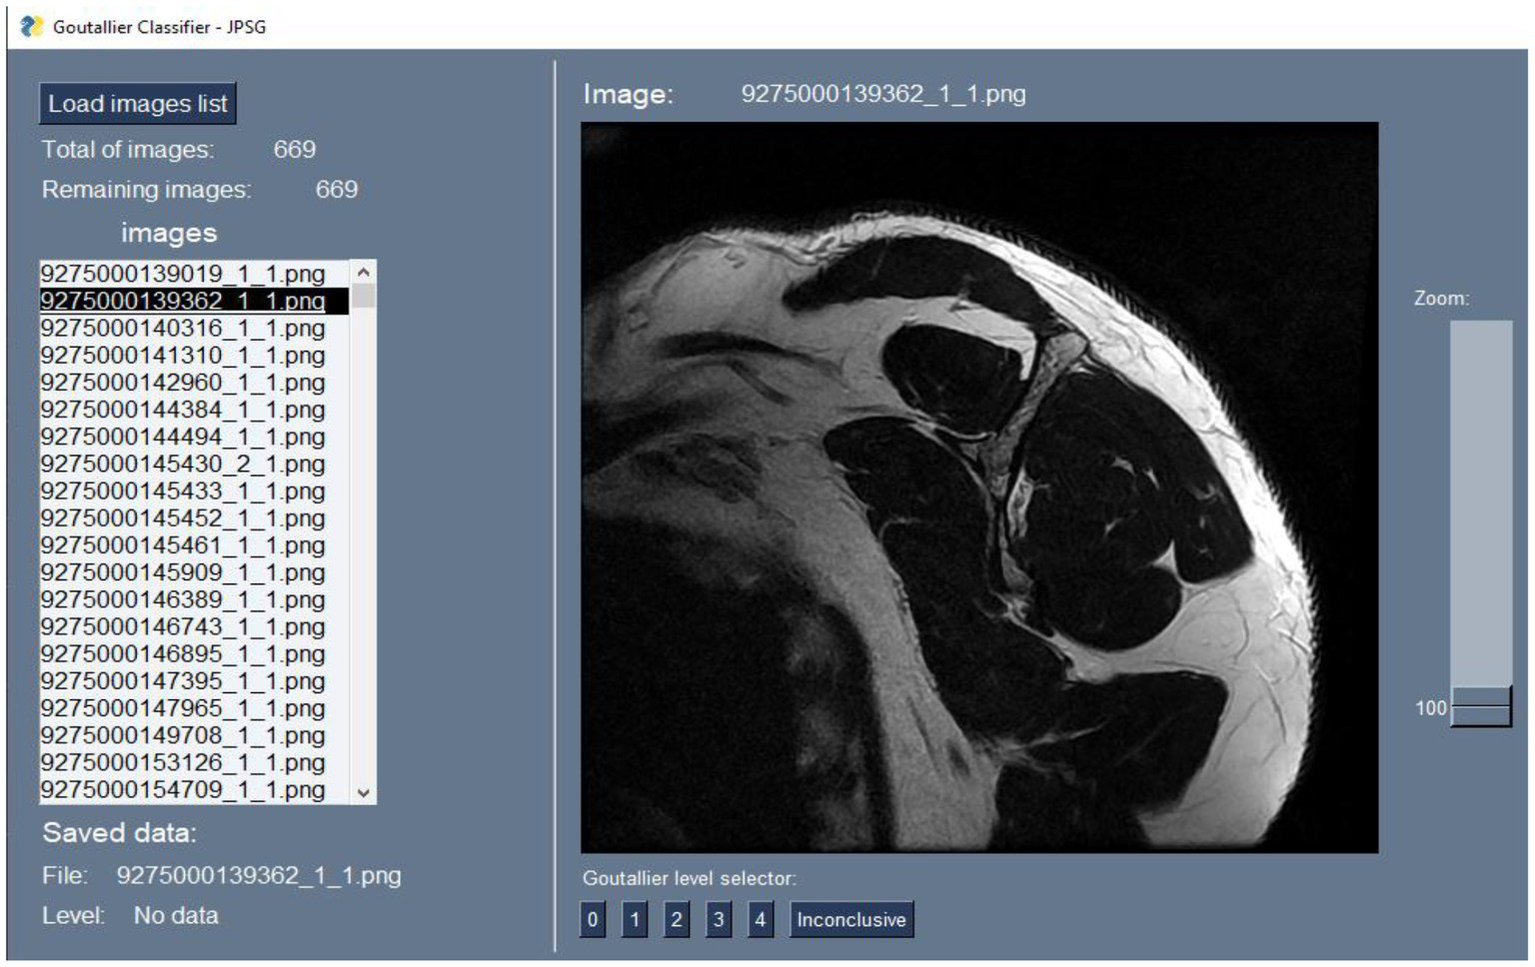

To perform the labeling process, we developed a simple Python software, Figure 2, that reads a folder with all the images to be annotated and then shows the MRI image one at a time. The radiologist selects the diagnosis for that MRI image. The program creates a two-field JSON file with the decision made for the professional for each image. One field is the image ID, and the other is the label record selected by the radiologist. These labels are our study’s ground truth.

Figure 2

Custom software interface.